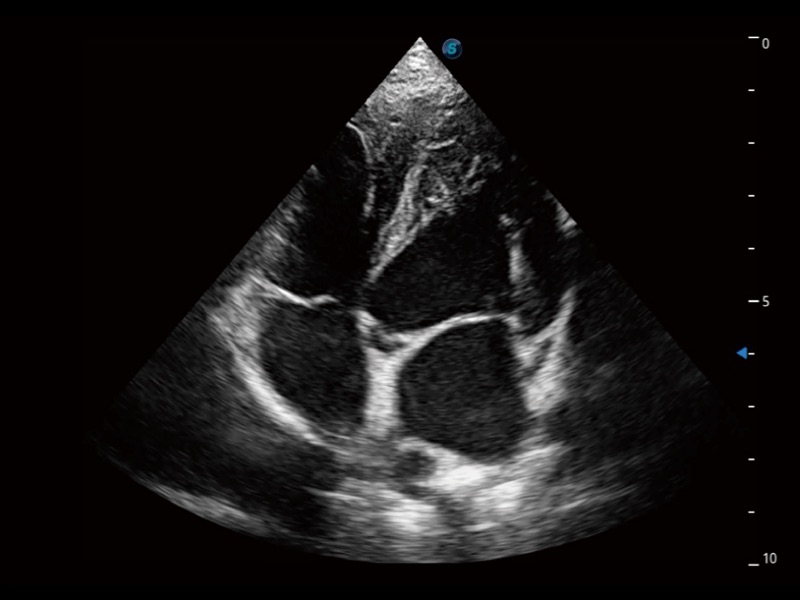

通过360度任意调节3条M型取样线,在同一心动周期上观察心脏不同位置的运动曲线,得到准确的心功能测量数据,有效评估心肌运动及左心室功能。

ProPet 70专为动物医生设计,对不同的动物体型和生理结构作出了针对性的优化。通过动物影像专用软件,可满足个性化的应用需求,帮助动物医生获得更精确的诊断数据。